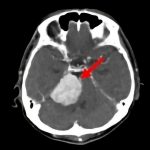

病名

断層撮影